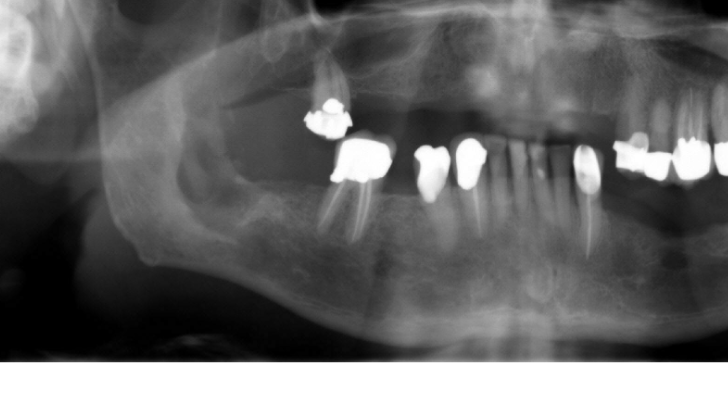

Osteomyelitis - Imaging

A

Radiographic images lag behind the clinical presentation since cortical involvement is required for any change to be evident.

Acute osteomyelitis often appears normal radiographically

Till at least 30-60% destruction of mineralized portion of bone takes place – this destruction is not visible on radiograph.

Chronic osteomyelitis – moth eaten appearance

Q

– what is recommended initially?

– Gives information of?

– Orthopanoramic view is recommended initially

– Easily obtainable

– Gives information of possible sources and progression.

25

chronic osteomyelitis-moth eaten